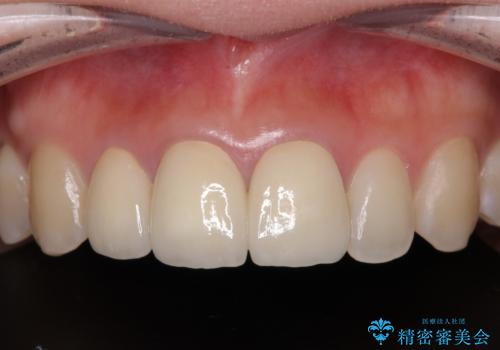

前歯の黒い縁を綺麗にしたい 前歯のオールセラミック

金属を除去したことで、周りと調和した自然な色合いとなり、クラウンの際の位置も歯肉に少し入り込む位置となっているためまるで本物の歯のような仕上がりとなりました。